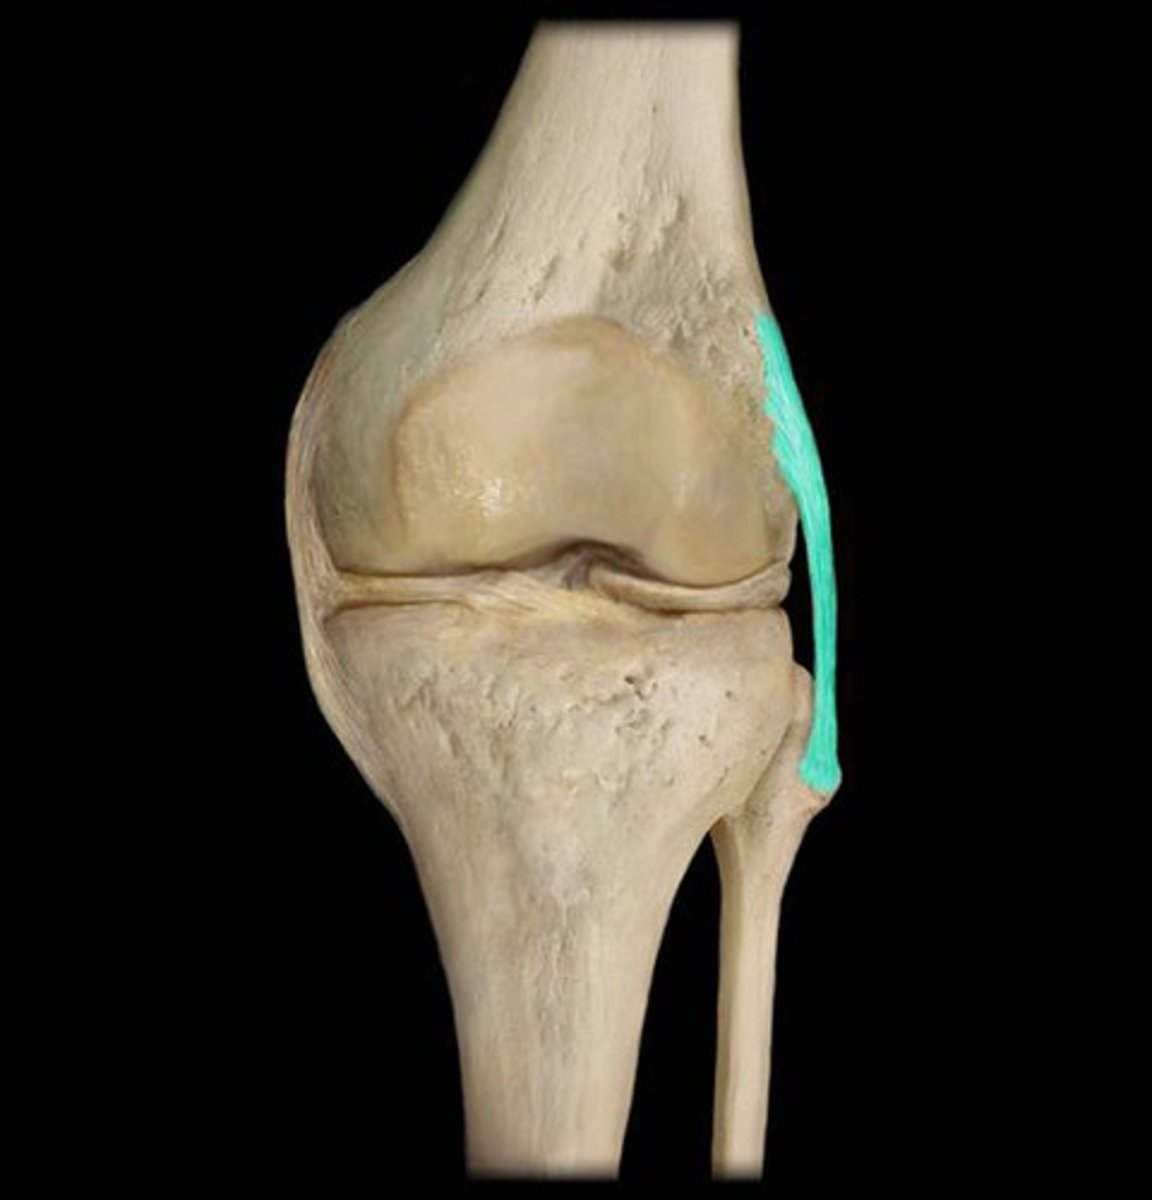

ligaments

fibrous bands that connect bones and bones/cartilages

hinge

synovial joint between bones (as at the elbow, knee, or finger) that permits forward and back swinging motion in only one plane